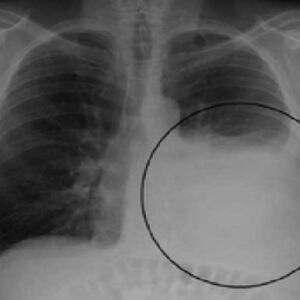

Rak pluća je najčešća vrsta raka, a u 81,7 posto slučajeva uzročnik je pušenje. Ono se povezuje sa 73,8 posto slučajeva raka grkljana, 50 posto raka jednjaka i 46,9 posto raka bešike.